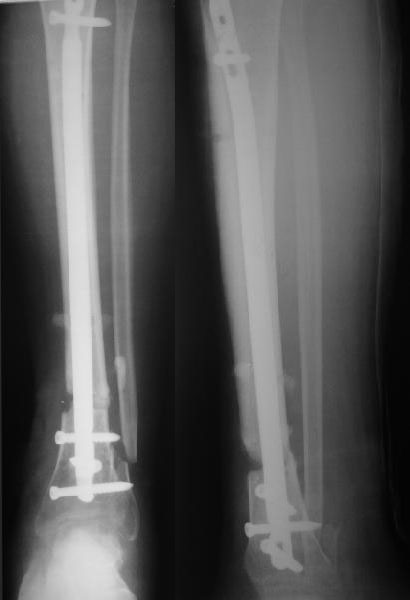

Давность травмы 3 недели. Синтез 17.10.2006. На счет большего угла: гипс наложен сразу после травмы - по разнице углового смещения можно судить о подвижности отломков и величине деформации.Сторонники варианта 4 ссылаются на данные мировой литературы(?), в которых якобы 50% интрамедуллярного остеосинтеза голени обходится без дистального блокирования.Неуверен о каких штифтах и переломах идет речь, но по-моему представленный случай не из этой серии.

Да, с устранением деформации проблем не должно быть. Но как будете вводить дистальные винты опять без усилителя рентгеновского изображения? Может, есть возможность перевести пациента для этой манипуляции в РКБ? Я слышал, там теперь есть ЭОП.